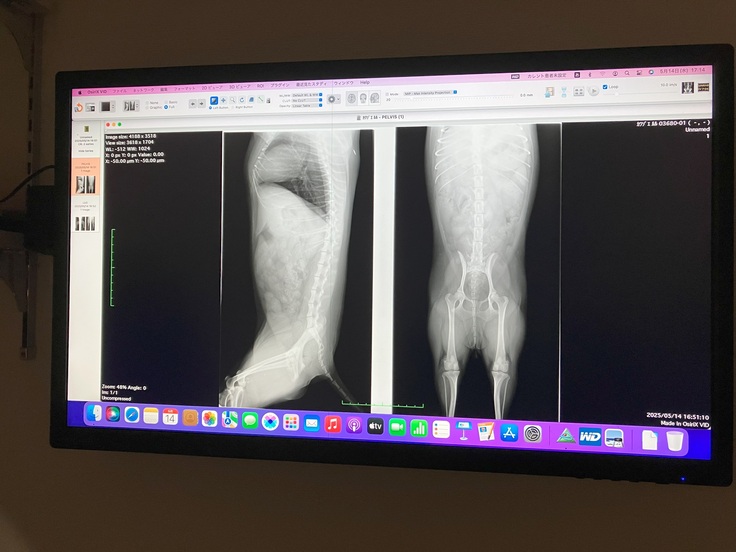

先生から別の病院で詳しく検査したほうがいいと言われたため、後日別の病院で検査したところ、両膝ともパテラ(グレード2~3の中間)と診断されました。

検査時のレントゲン1

検査時のレントゲン2